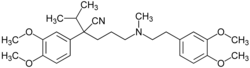

Das Diffusionsvermögen eines Moleküls durch die Endothelien der Blut-Hirn-Schranke wird vor allem durch seine Fettlöslichkeit (Lipophilie) und Größe bestimmt. Durch eine Modifizierung des Moleküls mit lipophilen Gruppen kann deshalb eine verbesserte Gehirngängigkeit erreicht werden.[33] Ein klassisches Beispiel hierfür ist die Di-Acetylierung des Naturstoffes Morphin zu Diacetylmorphin (Heroin). Heroin (log P=1,12) zeigt gegenüber Morphin (log P=0,2) eine über 25fach höhere Aufnahme im Gehirn (siehe dazu: Tabelle 1).[34] Entsprechende Ergebnisse werden beim Brain-Uptake-Index (BUI) für radioaktiv markiertes Morphin, Codein und Heroin erhalten, das in die Halsschlagader injiziert wird. Für Morphin liegt der BUI unterhalb der Nachweisgrenze, bei Codein bei 24 % und für Heroin bei 68 %.[35]

Dieses Prodrug-Konzept kann selbst bei peptidischen Wirkstoffen zu einer Verbesserung der Gehirngängigkeit führen.[36]

Das Konzept versagt allerdings bei Molekülen mit einer molaren Masse größer als 500 g·mol−1, da solche Substanzen aufgrund ihrer Größe nicht mehr die Blut-Hirn-Schranke per Diffusion passieren können. Zudem geht mit der Lipophilisierung eine deutlich schlechtere Löslichkeit des Wirkstoffes einher. Bei der oralen Gabe können aber nur gelöste Wirkstoffe im Gastrointestinaltrakt aufgenommen werden. Die Lipophilisierung bewirkt natürlich auch eine erhöhte Aufnahme in anderen, nicht zerebralen, Zellen. Auch gegen Efflux-Transporter, die den eindiffundierten Wirkstoff wieder aus dem Endothel ausschleusen, ist die Lipophilisierung wirkungslos.